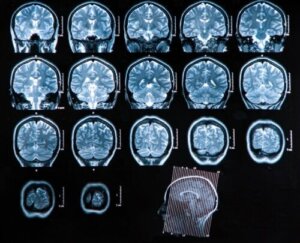

Rozpoznanie ropnia mózgu

Można przeprowadzić różne badania, które przybliżą lekarza do diagnozy i etiologii, aby mógł określić dalsze leczenie. Do dostępnych obecnie technik należą:

- Tomografia komputerowa: ma dużą przydatność diagnostyczną, ponieważ pozwala sprawdzić wszelkie powiązania ze stanem chorobowym i ustalić leczenie zgodnie z odpowiednią fazą. Ta technika jest również dobrym badaniem do śledzenia ewolucji patologii po wdrożeniu leczenia.

- Rezonans magnetyczny: jest to najlepszy rodzaj badania obrazowego w diagnostyce ropnia mózgu. Jest znacznie bardziej czuły niż tomografia komputerowa i oferuje wiele zalet w wykrywaniu wczesnego zapalenia mózgu i obrzęków oraz lepszego różnicowania obszarów zapalnych i innych dotkniętych struktur.